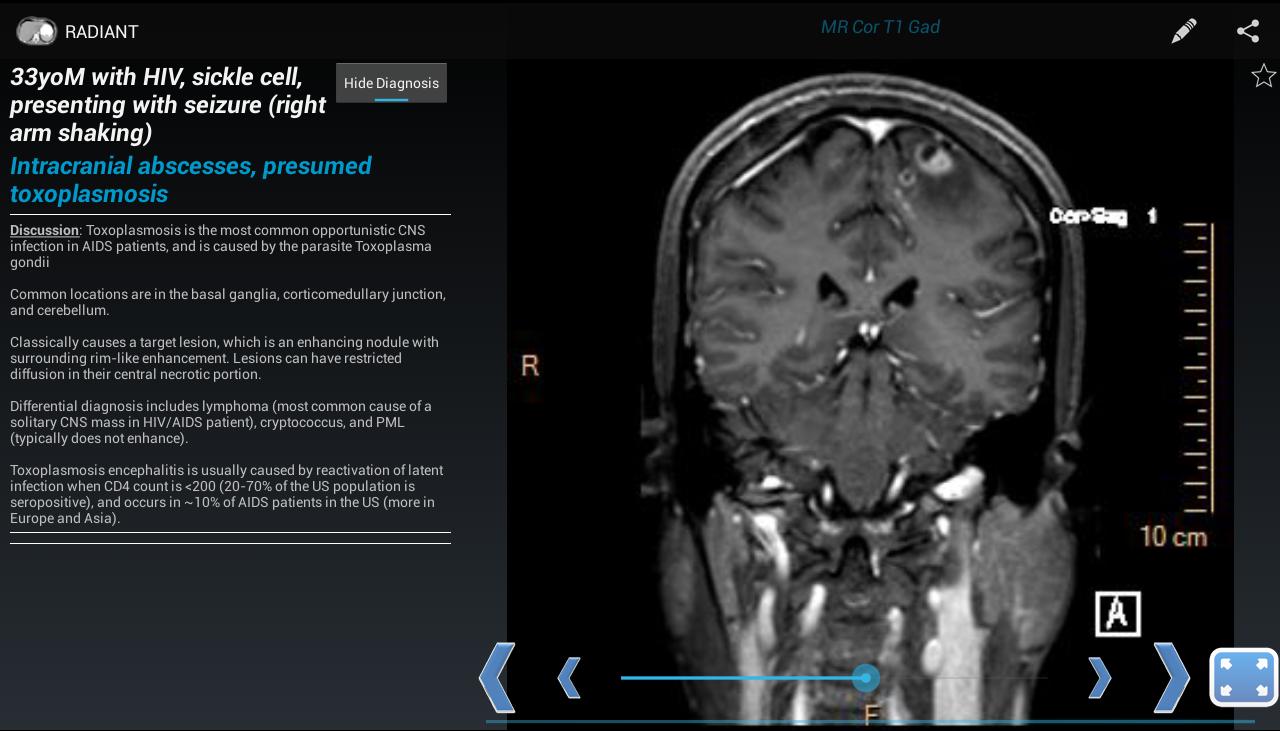

Create, view, and share interactive, image-based radiology education content

RADIANT is a platform to create, manage, and share image-based educational materials, primarily intended for users in the medical field. It is ideal for sharing interesting cases among diagnostic radiology residents, fellows, medical students, and faculty. It is NOT meant to be used for diagnosis.

With RADIANT, you can create cases showing x-rays, ultrasound, CT, MRI, or any other imaging modality. It is a great way to learn chest x-rays, normal anatomy, and common disease processes, using real, high-quality diagnostic medical images.